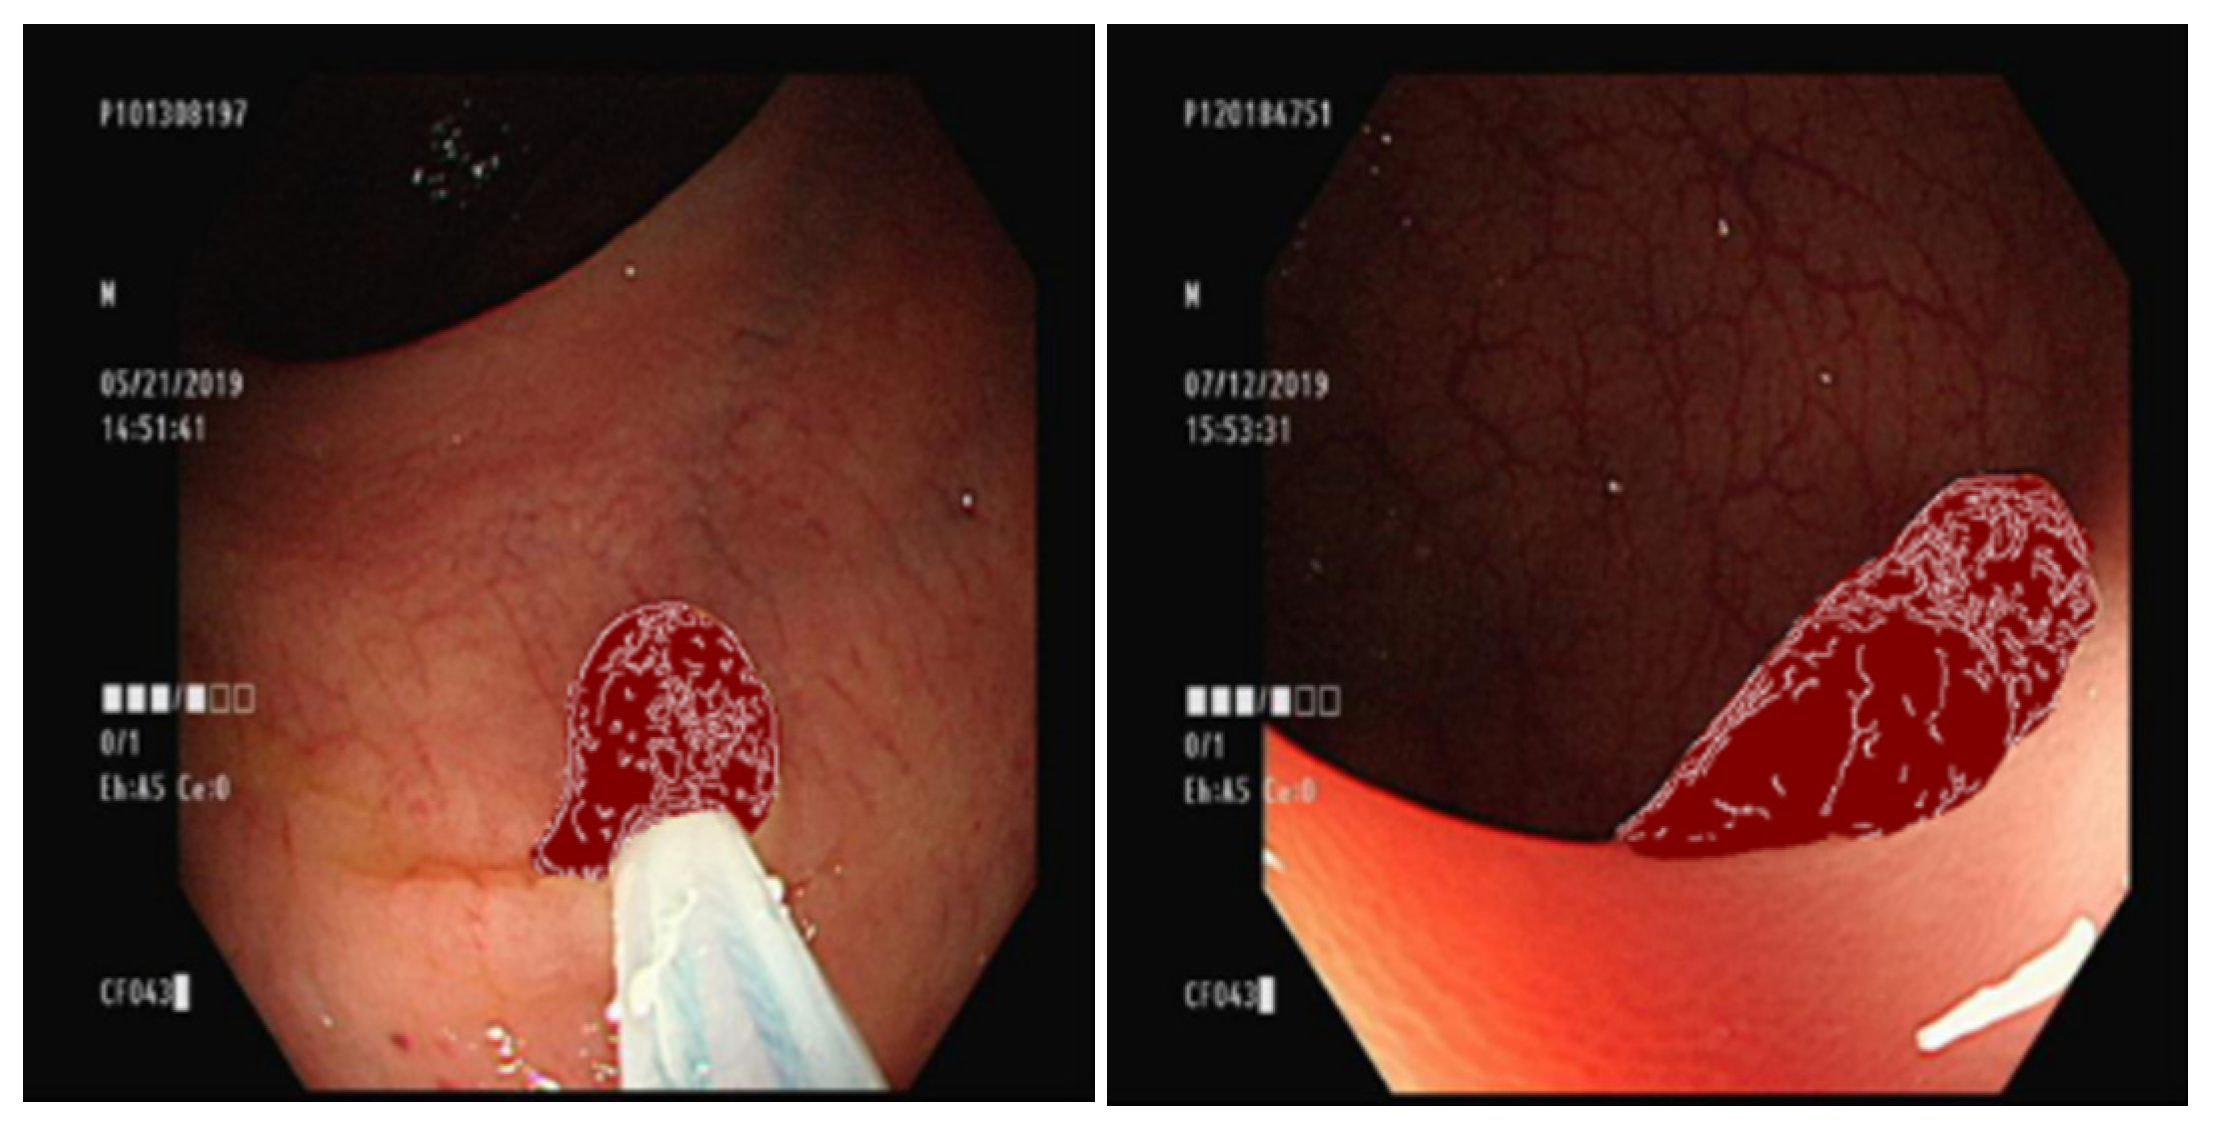

3.5. Overlaying the Ground Truth Map onto the Original Image

3.6. Conditional GAN Architecture

3.7. Comparison of GAN Output

4.1. Comparison of GAN-Generated Images